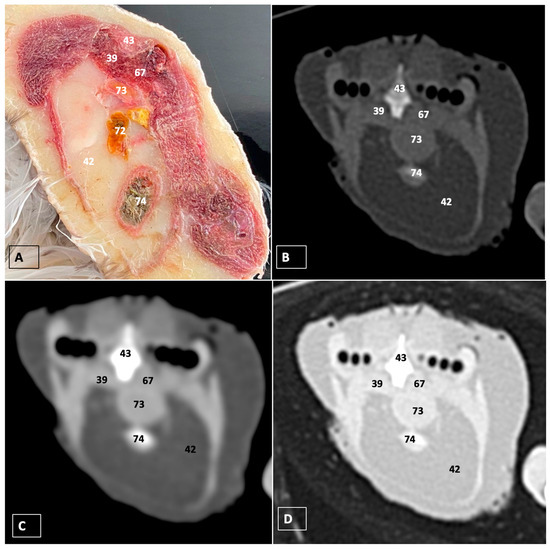

3.1. Anatomical Dissections and Cross-Sections

3.2. Computed Tomography Images